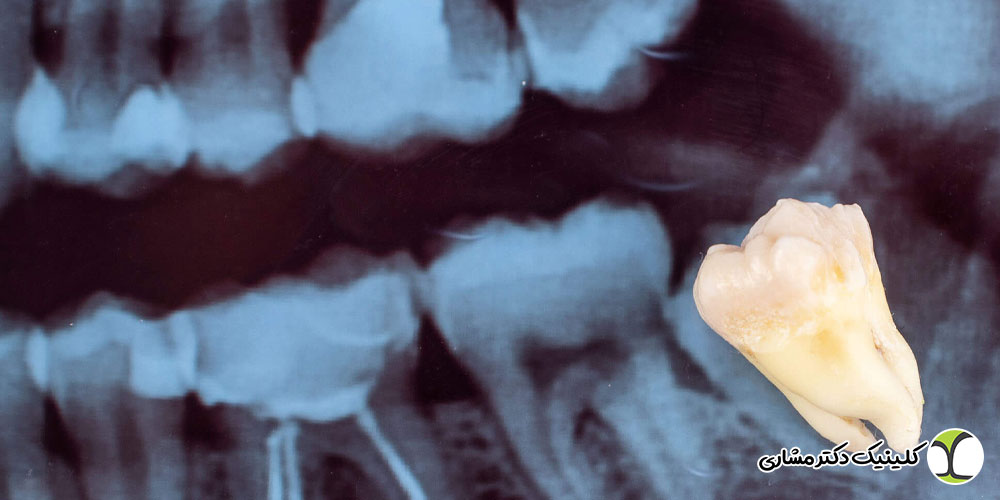

- ساختار ریشه: ریشههای دندان عقل اغلب دارای شکلهای منحنی یا غیر منظم بوده و تعداد و ساختار کانالهای عصبی میتواند پیچیدگی بیشتری نسبت به سایر دندانها داشته باشد.

متخصص با استفاده از ابزارها و تکنیکهای تخصصی، به کانالهای ریشه دندان عقل نفوذ کرده و تمامی بافتهای عفونی شده یا مرده پالپ و عصب را خارج میسازد. به دلیل پیچیدگی ریشههای دندان عقل، این مرحله از حساسیت بالایی برخوردار است. کانالها با دقت کامل شستشو و ضدعفونی میشوند تا هیچ میکروب یا بافت آلودهای باقی نماند. در بسیاری از کلینیکهای تخصصی مانند کلینیک دکتر مشاری، از تکنولوژیهایی مانند میکروسکوپهای دندانپزشکی برای افزایش دقت بصری، اطمینان از یافتن تمام کانالها (حتی کانالهای فرعی) و جلوگیری از خطاهای احتمالی در حین کار استفاده میشود. این مرحله ضامن موفقیت طولانی مدت درمان ریشه است.